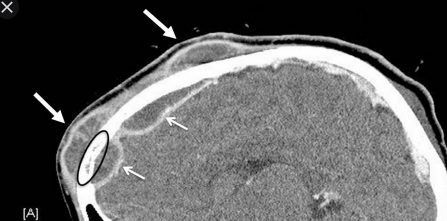

Pott Puffy Tumor

- Abcès épicranien

- Complication d’une sinusite frontale

- Souvent abcès épiduraux associés (ou abcès sous-duraux)